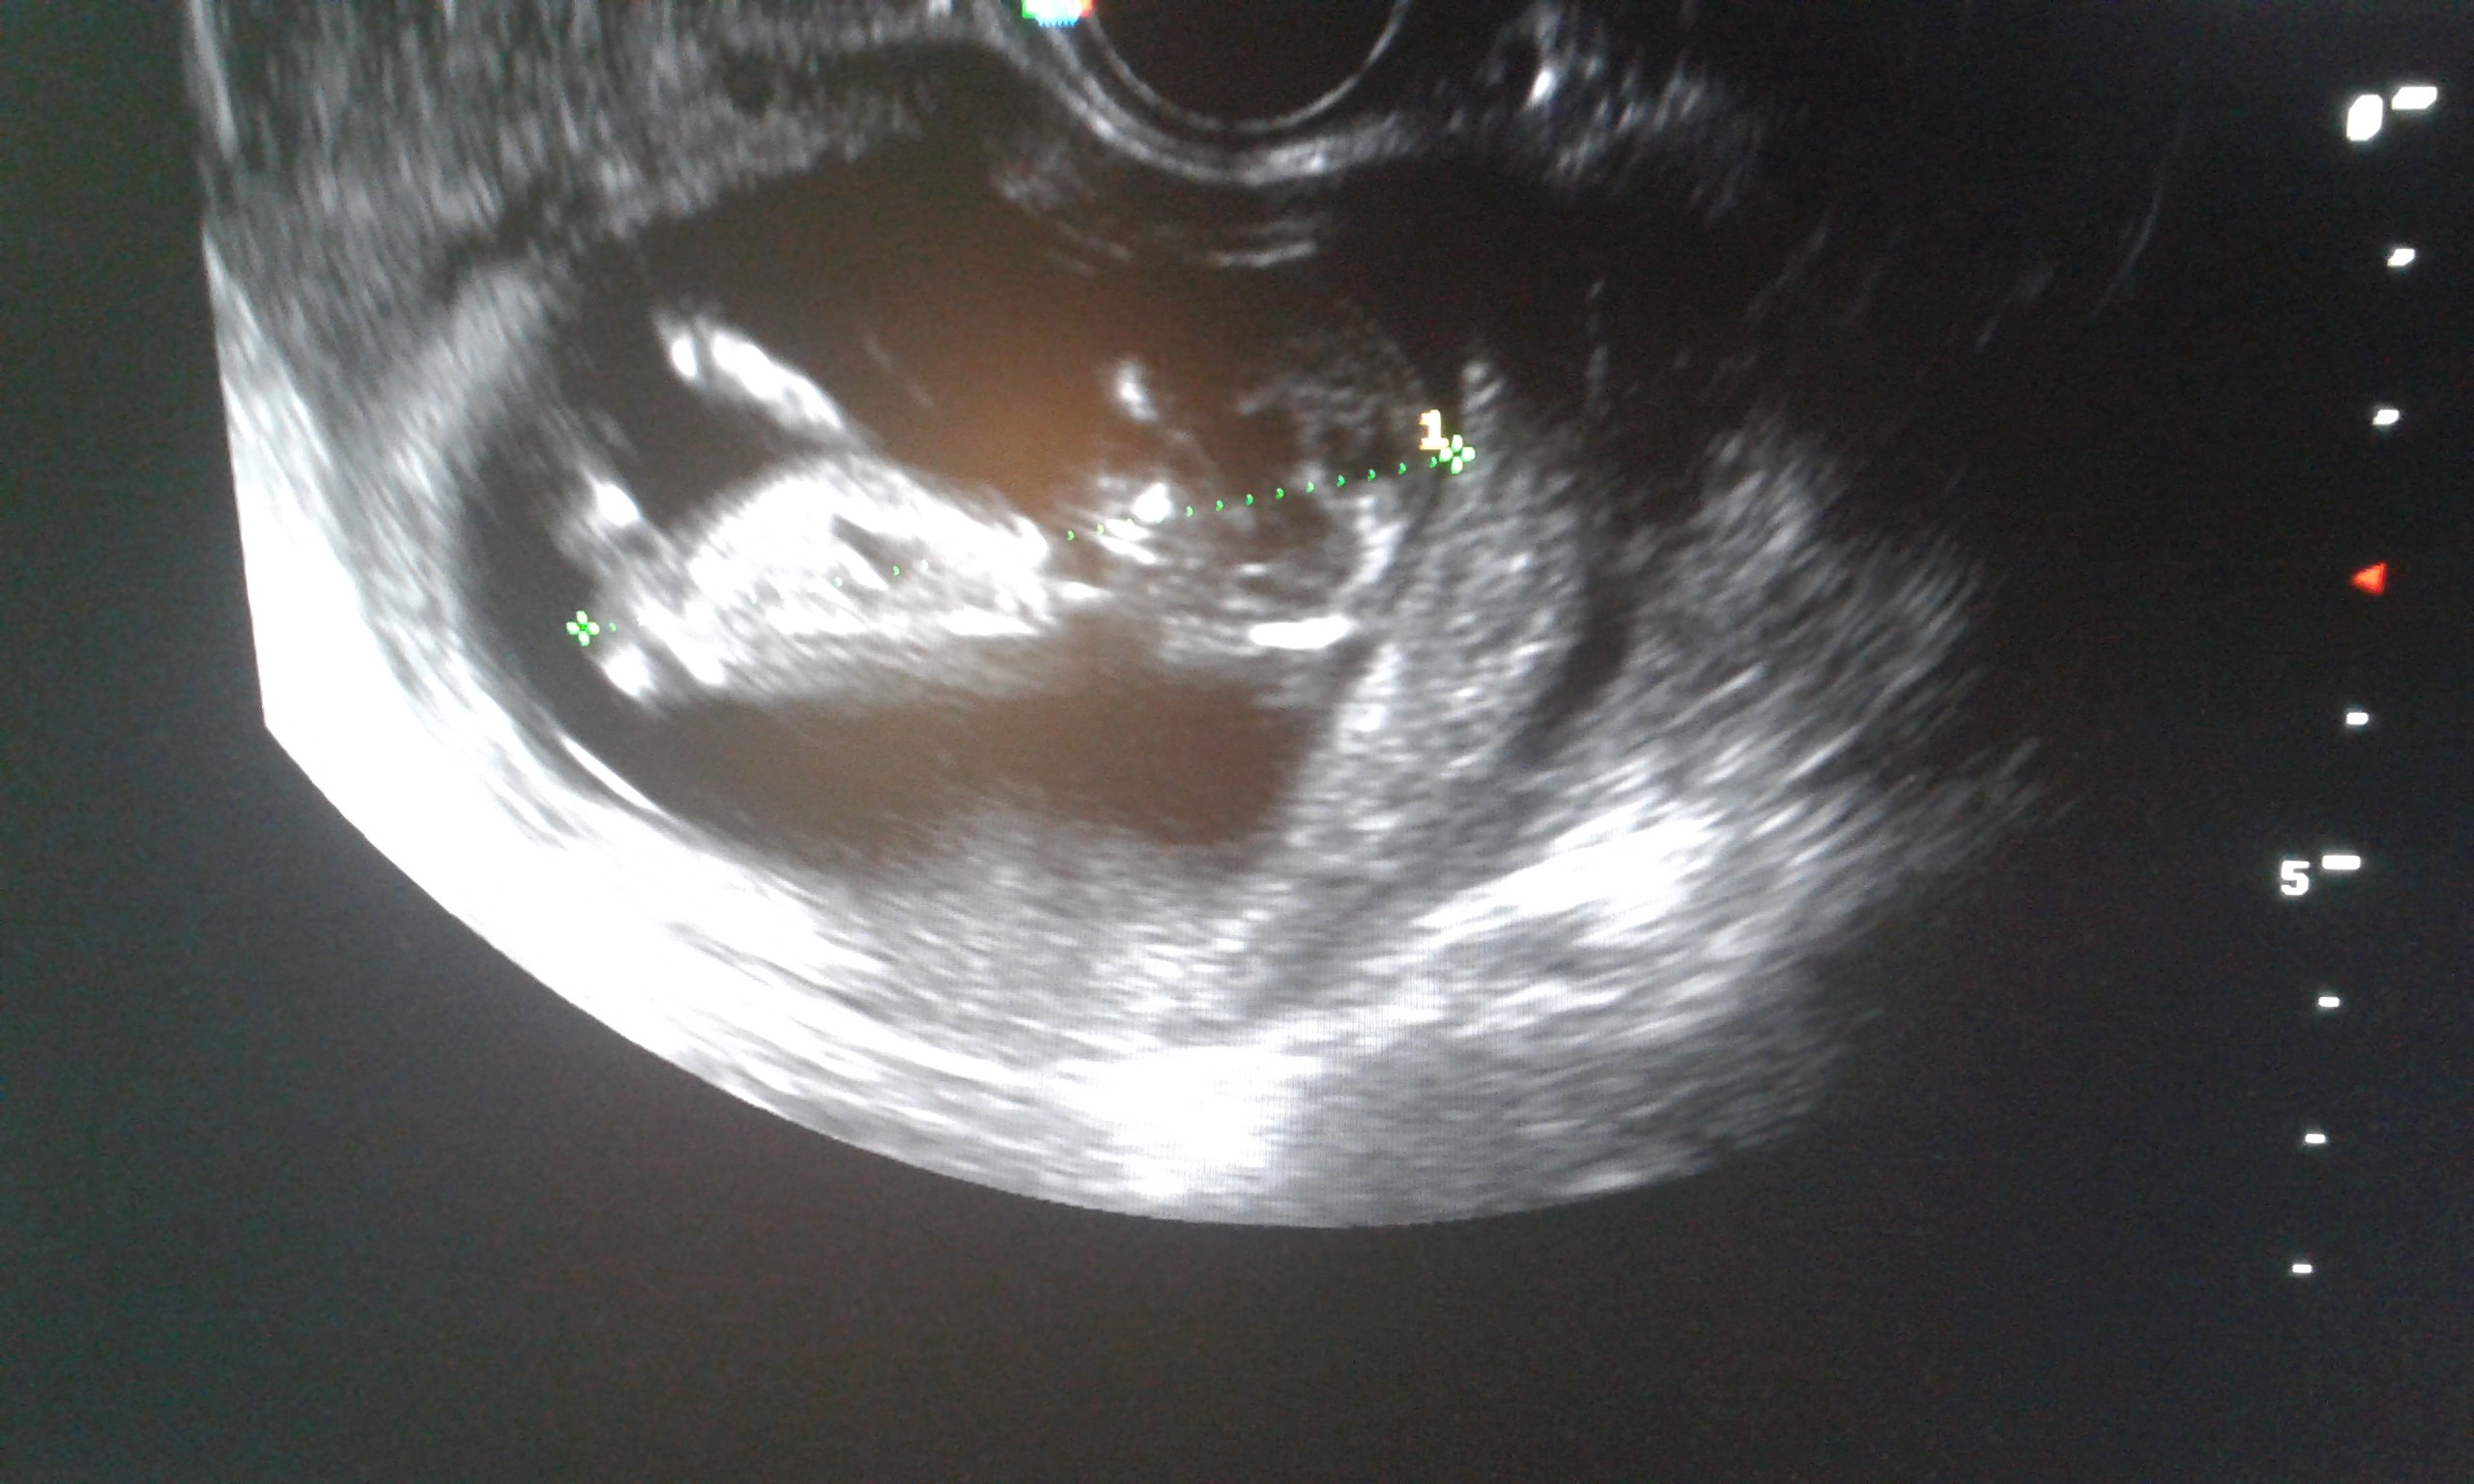

jest malusi pęcherzyk ciążowy i zarys pęcherzyka żółtkowego

niestety są też 4 torbiele na jajnikach :(

Byłam dziś na kontrolnej wizycie☺ mój bąbelek ma 13 tygodni i podobno to chlopiec☺ dziś to ja się popłakałam jak widziałam jaki ruchliwy jest mój skarb. Mąż się ze mnie śmieje ale w pewnym momencie było jakby maluszek pomachal do nas

• 20180607_150927.jpg